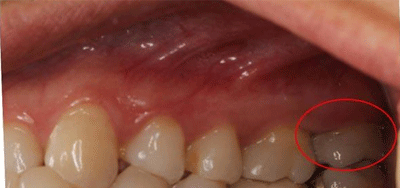

术后CAD/CAM全瓷嵌体修复